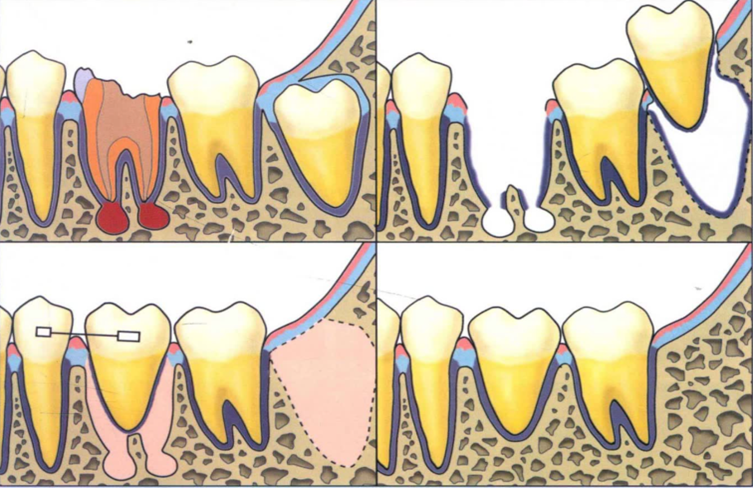

自体牙移植是将天然牙(废用牙,常常是智齿)移植到一个缺牙位置,让其在新的位置发挥作用。这种移植的天然牙和种植牙在咬合感受上有很大的区别,优点显著,美学效果较好。移植后的牙齿是可以移动的,如果后续需要矫正,也可以进行拉动,而种植牙是完全不可能。其次就是年龄限制,种植牙仅限于成年人,但自体牙移植的年龄没有严格限制,这就为那些青少年受过伤的无法保留的牙提供了一个好的机会。这么多的优点,为何自体牙移植不火起来?不被口腔医生使用?因为它的操作不可预测性,及成功率不到50%,这让口腔医生望而却步。

然而,随着计算机技术的高速发展,自体牙移植技术聚集了目前大部分口腔先进治疗技术,如微创拔牙术、牙槽骨及牙周组织再生技术、数字化导板技术和种植技术等等,目前成功率可以达到86.67%,存留率达96.67%。有学者进行15年随访,成功率可以达到81%,存留率达88.37%。本科室组织口腔各科室专科专家进行术前讨论,已通过计算机数字化辅助技术,利用3D打印技术制作智齿模型,在数字化导板引导下精准备洞,调整空缺位置,给智齿建成一个合适的“新家”,给它一次做有用牙齿的机会。本科室对自体牙移植具有丰富的经验,预后较好,获得了患者的认可和好评。